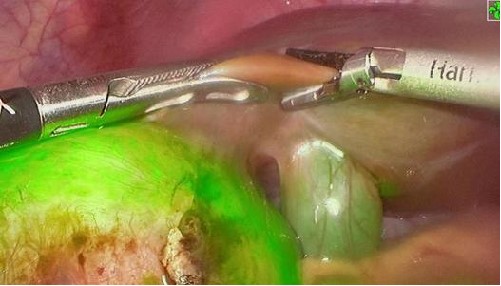

脑胶质瘤是脑部最常见的原发性肿瘤,占中枢神经系统恶性肿瘤的81%。目前,脑胶质瘤的治疗仍以手术为主导。然而,手术在完全切除肿瘤方面常面临挑战,有时甚至难以实现。近年随着荧光成像技术在恶性脑胶质瘤精准手术中的广泛使用,使得瘤切除术肿瘤切缘可视化成为可能。但目前临床常用的荧光造影剂存在给药到手术时间不确定的问题,可能造成病灶与正常组织对比度不足,影响术中的病灶的判断。

PL002是浙江普利药业有限公司研发的荧光/磁共振双模态造影剂,荧光/磁共振双模态造影剂的成功研发将成为提高脑胶质瘤手术效率的有效方案。术中荧光技术与核磁共振成像的结合,相较于单独使用,能够更准确地识别肿瘤组织与功能区的位置关系,以及患者的肿瘤浸润边缘。这种联合使用不仅能在保留患者功能的前提下实现功能区脑胶质瘤的最大限度安全切除,还能有效降低术中神经损伤的风险。

去年10月,PL002已经获得FDA签发的美国药物临床试验批件,用于原发性肝癌患者的术前诊断及术中导航。此次在国内申报的适应症为脑胶质瘤患者的术前诊断及术中导航。相较于原发性肝癌,脑胶质瘤对于切除精度要求更高,尤其是临近重要功能区的时候,因此对精准诊断的造影剂的临床需求更为迫切。